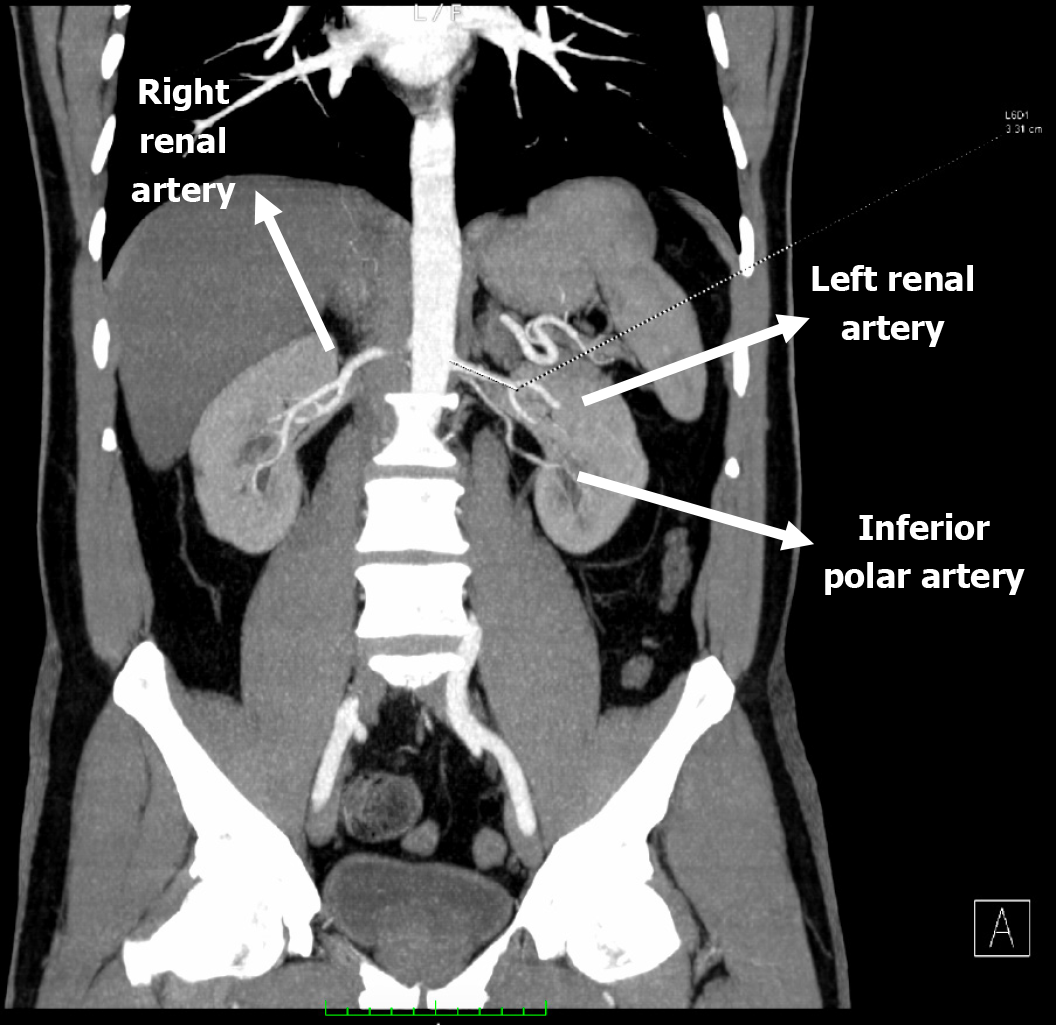

Figure 1

Computed tomography angiography scan depicted the anatomical configuration of the donor renal arteries.